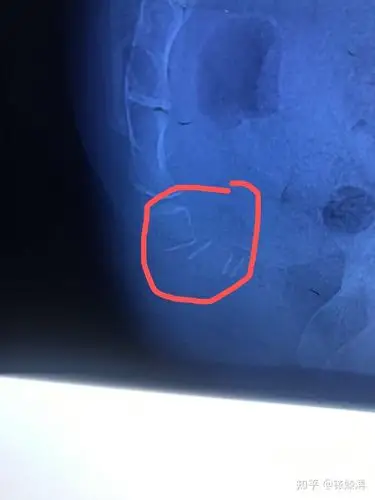

尾骨陈旧错位疼的厉害